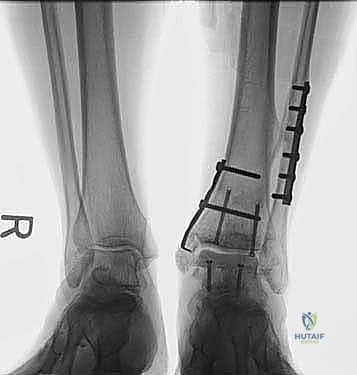

- في بعض الحالات المعقدة، قد يتطلب الأمر إجراء قص عظمي في الكعب (Malleolar Osteotomy) لفتح المفصل بالكامل ورؤية السطح المتضرر بوضوح، ثم يتم إعادة تثبيت هذا العظم لاحقاً.

4. زراعة الطعم وتثبيته (Graft Implantation and Fixation)

- يتم تشكيل الطعم المأخوذ من المتبرع ليطابق الحفرة التي تم إعدادها في كاحل المريض تماماً (مثل تركيب قطعة البازل).

- يتم إدخال الطعم برفق (Press-fit).

- لضمان الثبات التام، يتم تثبيت الطعم باستخدام براغي دقيقة جداً (غالباً تكون قابلة للامتصاص البيولوجي أو براغي تيتانيوم غاطسة تحت مستوى الغضروف حتى لا تحتك بالمفصل).

صور إضافية من داخل غرفة العمليات والخطوات الجراحية

ندرك أهمية توثيق الخطوات الجراحية لطلاب الطب والمرضى الراغبين في فهم دقة الإجراء. هذه الصور توضح مراحل زراعة وتثبيت الطعم العظمي الغضروفي بدقة متناهية تحت إشراف أ.د. محمد هطيف.